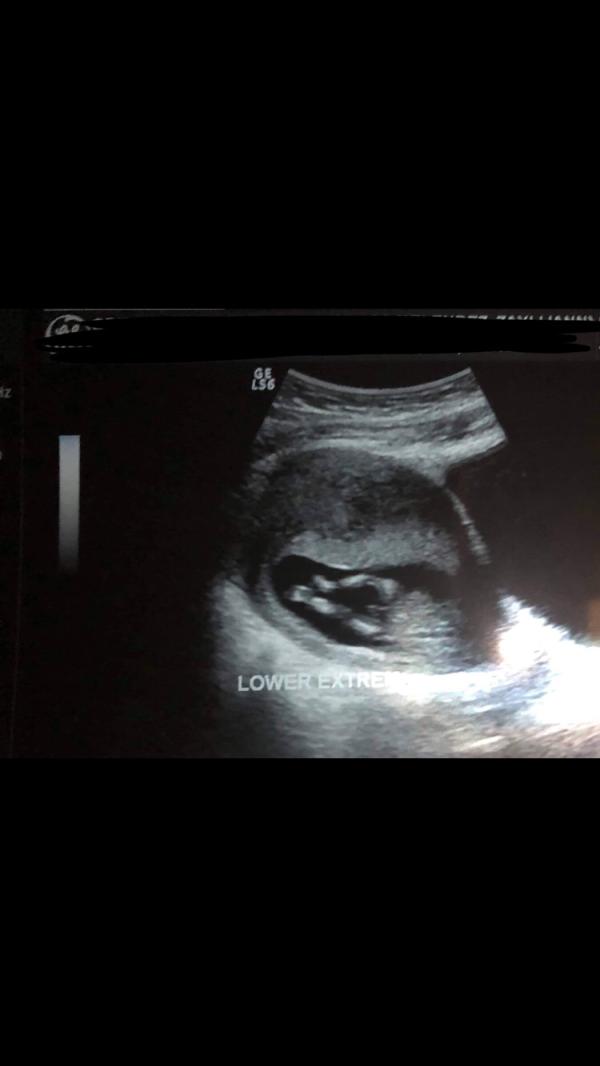

My friend is 13wks. Do y’all think it’s boy or the unbiblical cord??

That’s cord. The penis and testicles would look more attached and be the same shade of grey (echogenicity) as the abdomen, of not brighter. But it’s also still early for gender to be 100% apparent, so it’s still possible that it is a boy, just not based on this image.

I do ultrasound, no OB, though I had some training in it when learning fetal echo

I don’t think anyone could positively say it’s a boy LOL that must have to be the umbilical cord because it practically hangs down to his knees.

Lol that has to be a unbiblical cord that’s a big weewee for a baby boy 😶🤦♀️😂